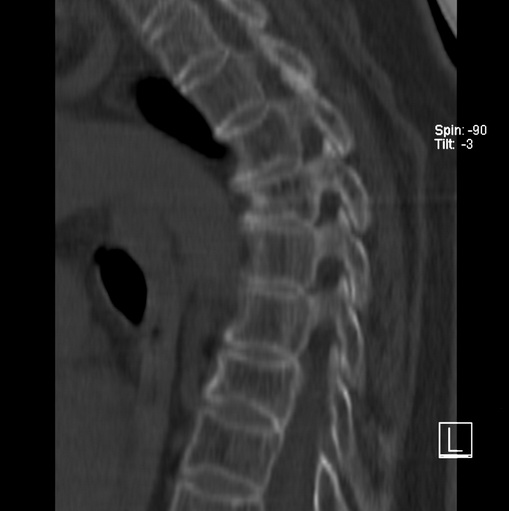

女、73、胸痛、胸闷3个月,无明显外伤病史,x线疑t4、t7陈旧压缩骨折,ct未经明显骨折,请问结论如何报?

老年女性病人,骨质稀疏,有些驼背,t4明显变扁,t7略变扁,椎体边缘无中断,骨小梁排列正常,无嵌插所致致密线。结合无明显外伤史,考虑老年骨质稀疏,慢性压缩改变,正如老年人骨质稀疏椎体呈双凹改变一样。我考虑报:老年骨质稀疏,t4、t7楔形变,脊柱曲度改变(驼背).敬请大家指教。